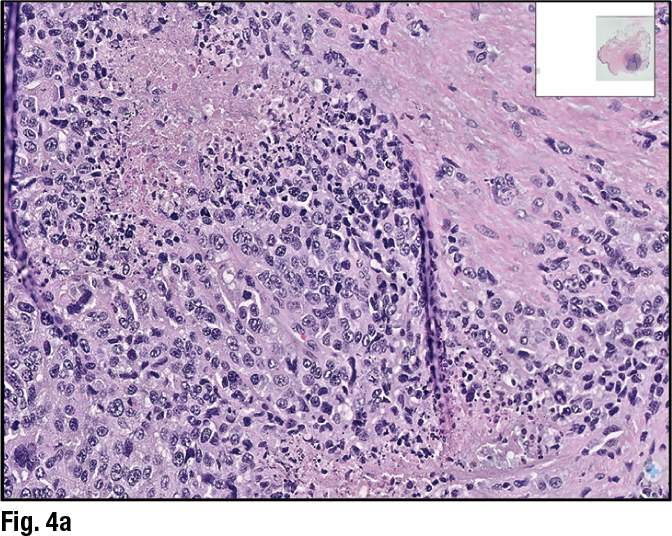

Dr. Collins described the mastectomy specimen as having “sheets of tumor cells.” On high power, “you see these are very atypical cells with large pleomorphic nuclei,” she said, and areas of necrosis and mitotic figures (Fig. 4a). Yet some areas appeared “slightly more spindled.” (Fig. 4b).

Given this different morphology and the poor response to the neoadjuvant chemotherapy, the original pathologist wondered whether the lesion might be a malignant melanoma. The pathologist used melanoma markers, Dr. Collins said, showing an image of the positive Melan A stain (Fig. 5). “So this is an example of a metastatic melanoma to the breast that had been diagnosed as a triple-negative breast carcinoma and treated with neoadjuvant chemotherapy.” Melanoma is not a carcinoma but can appear epithelioid, as it did in this case. “We teach our trainees that melanomas are the great mimicker; they can look like anything,” she says.